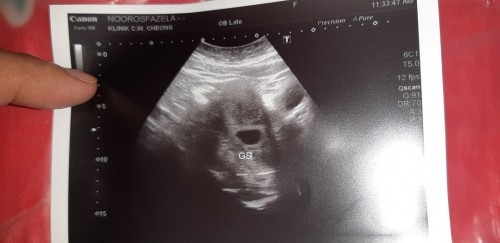

Alhamdulilah penantian 15tahun...first baby harap2 kekal..mummy2 doakan sy ya kuat.. 5week++